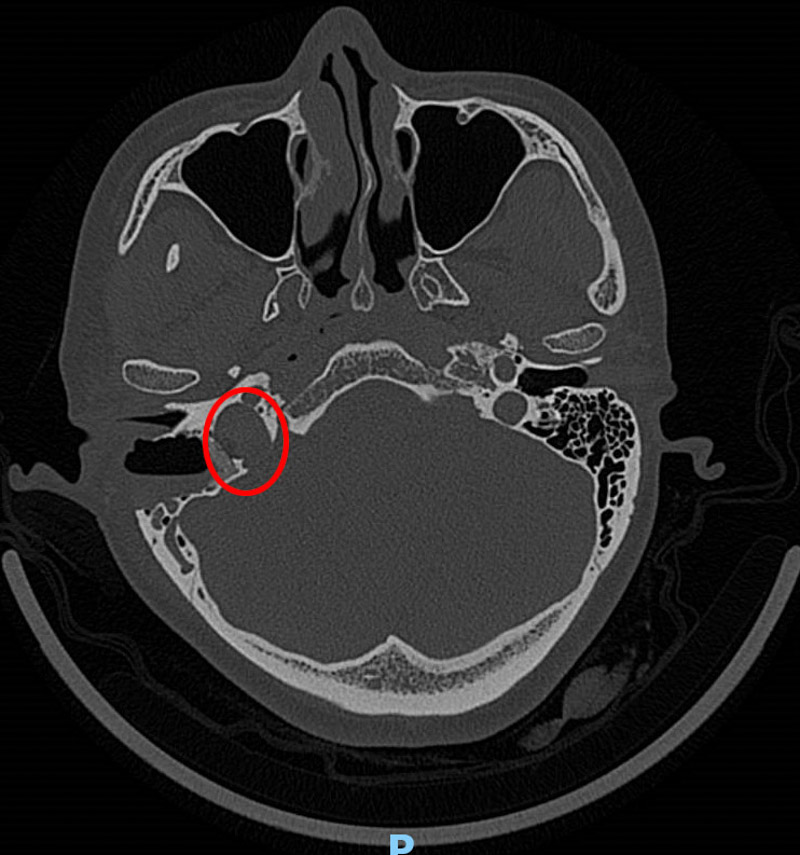

接診醫(yī)生了解情況后,為韋女士做了耳內(nèi)鏡及聽(tīng)力學(xué)檢查,并沒(méi)發(fā)現(xiàn)異常,但根據(jù)患者的實(shí)際情況并結(jié)合多年的經(jīng)驗(yàn)判斷,患者的右耳有可能患有血管搏動(dòng)性耳鳴。為了進(jìn)一步證實(shí),患者進(jìn)行了高分辨頭顱CT檢查,果不其然,放射科醫(yī)生在CT影像學(xué)中發(fā)現(xiàn)了蛛絲馬跡:患者的右側(cè)頸靜脈球高位,可疑合并前壁和外側(cè)壁缺損。這就是導(dǎo)致韋女士耳鳴的罪魁禍?zhǔn)祝?/span>

搏動(dòng)性耳鳴是一種有節(jié)律的耳鳴,由患者頭頸部血管或肌肉產(chǎn)生,并通過(guò)骨骼/血管和血流傳導(dǎo)至耳蝸而感知,患者自述耳內(nèi)有如同心臟或血管脈搏跳動(dòng)頻率一致的耳鳴聲。搏動(dòng)性耳鳴的病因較多,多與血管相關(guān),臨床上頸靜脈球高位為較常見(jiàn)的病因之一。耳部結(jié)構(gòu)復(fù)雜、精細(xì),放射學(xué)醫(yī)師需要豐富臨床經(jīng)驗(yàn)及扎實(shí)的亞專(zhuān)業(yè)知識(shí),才能從影像學(xué)資料中找出耳部細(xì)微的病變部位和病變類(lèi)型。柳州市人民醫(yī)院放射科通過(guò)多年亞專(zhuān)科外派進(jìn)修及與臨床專(zhuān)科密切溝通,對(duì)類(lèi)似專(zhuān)科疾病的確診率大幅度提高,自年初至今發(fā)現(xiàn)類(lèi)似病例10余例,成功實(shí)施手術(shù)治療6例,術(shù)后均取得了較好的療效。